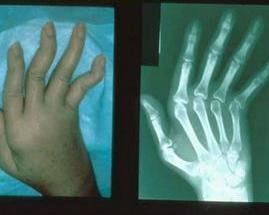

非淋球菌性细菌性关节炎是一种严重的疾病,病死率为5%~10%。25%~40%的患者有关节损伤与功能障碍。预后与多种因素有关,包括感染的长期性、细菌的特性、累及的关节、宿主的抵御能力以及一些治疗原则的应用等。但根据美国蒙大拿州立生物医学中心统计,即使得到及时有效的治疗,非淋球菌性化脓性关节炎仍比淋球菌性关节炎有更高的并发症、致残率及致死率。